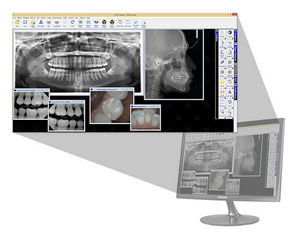

Desde la toma y edición de imágenes de rayos X y de la cámara, el intercambio de imágenes en la nube hasta la planificación de implantes y plantillas de taladrado: con VistaSoft confluyen todos los hilos del sistema de imágenes dentales. El principio ...